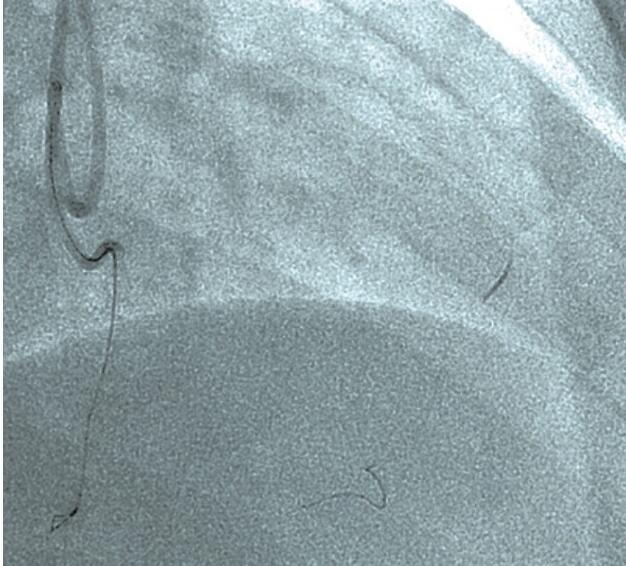

Retrograde CTO PCI in a Difficult-to-Cross Lesion

Chronic total occlusion (CTO) percutaneous coronary intervention (PCI) can be a challenging intervention. However, having the right equipment and tips/tricks for troubleshooting can simplify these interventions. We describe suggested equipment and ideas for troubleshooting in the case below.